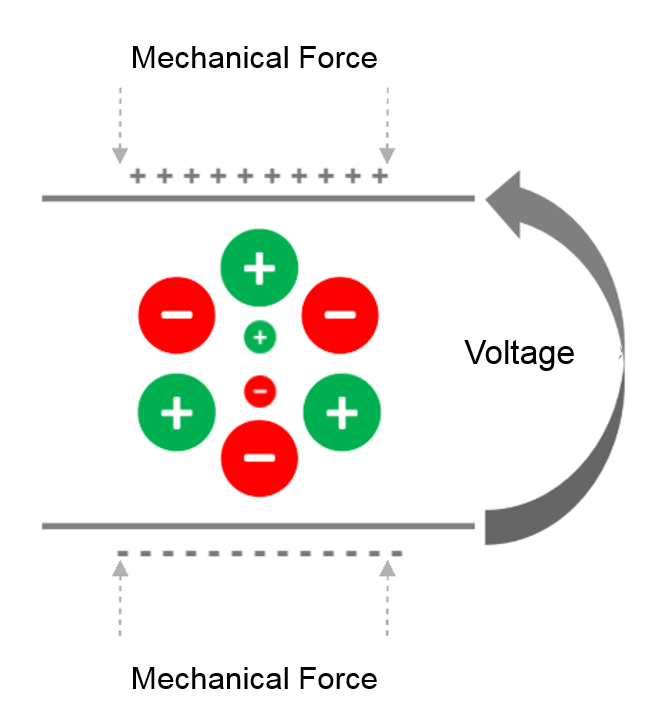

Direct Effect

The direct effect is the generation of an electrical signal following the application of a mechanical force. The piezoelectric effect converts the mechanical energy (received ultrasound wave), into electrical energy, due to the crystal deformation. This is how ultrasound transducers receive the sound waves.

It is known that the crystals in the ultrasonic probe change shape, and emit ultrasonic waves when stimulated by an electrical current. These sound waves reflect off the surface of the body and collide with quartz crystals, which then produce an electrical current.